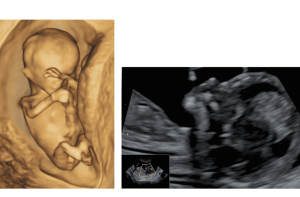

שקיפות עורפית היא בדיקת אולטרסאונד המתבצעת בשליש הראשון של ההריון – בין השבוע ה־11 לשבוע 13 ו־6 ימים.

הבדיקה אינה פולשנית, ולרוב מבוצעת בגישה בטנית. במידת הצורך, ובהתאם לתנוחת העובר ואיכות ההדמיה, ניתן לבצע את הבדיקה גם בגישה נרתיקית – כדי לקבל תמונה מדויקת יותר.

הבדיקה מתמקדת במדידת העובי של הנוזל התת-עורי באזור עורף העובר. מדידה זו נקראת "שקיפות עורפית" וניתנת כערך מספרי במילימטרים.